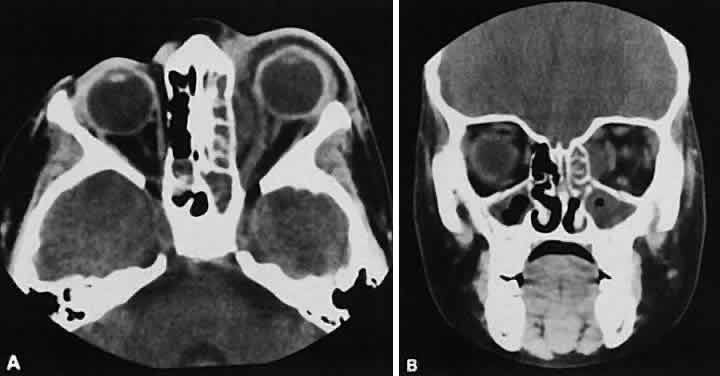

The edema and inflammatory infiltrate that accompany infections are indistinguishable from that associated with orbital inflammations. The presence of sinus disease, however, is a more constant feature with infections, because the sinus represents the infectious nidus in most cases (Fig. 9). In addition to the frequent appearance of sinus disease, the adjacent EOM is invariably enlarged. Less often, orbital infections may be transmitted through the blood, related to a retained foreign body, or spread from the lids. Chandler and colleagues47 classified orbital infections into five groups. Group 1 (preseptal cellulitis) represents inflammatory edema and reflects congestion of venous outflow. Group 2 has actual orbital infiltration/edema with mass effects and functional deficits. Group 3 includes patients with subperiosteal abscesses. Most of these dome-shaped subperiosteal abscesses are located along the medial wall. Group 4 includes patients with orbital abscesses who may display a ring-enhancing lesion with mass effect. Group 5 represents intracranial extension of the inflammation into the cavernous sinus or sinuses, which appear engorged and opacified.

Fig. 9. Orbital cellulitis. A. Axial view shows a subperiosteal soft-tissue mass displacing the medial rectus muscle. The ethmoidal sinus is opacified secondary to inflammatory disease, which invariably precedes the orbital inflammation. B. Coronal view further shows the subperiosteal and ethmoidal sinus inflammation. Inflammation changes also are seen in each maxillary sinus.

Harris48 related the clinical course of patients with subperiosteal abscesses to their CT scans. The sub-periosteal material could not be predicted from the size or the relative radiodensity of the collections on the scan. Serial scans also showed enlargement of the abscess during the first few days of intravenous antibiotic therapy, regardless of the ultimate response to therapy.